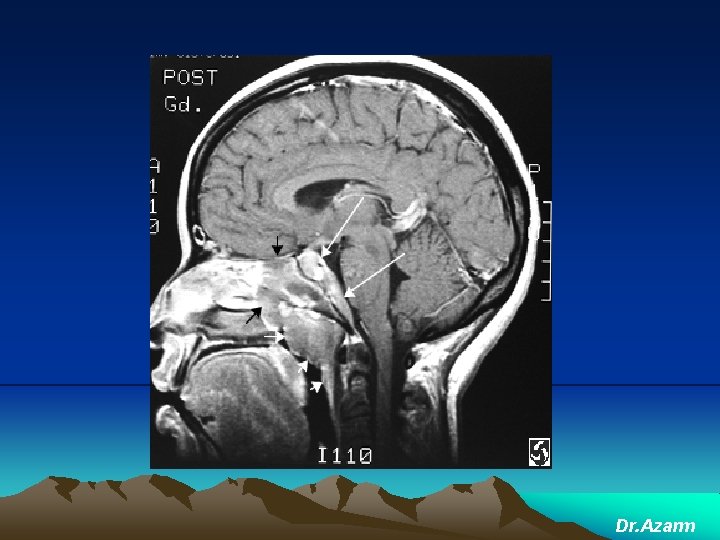

CNS lymphoma may affect people whose immune system is not working properly. for example, after organ transplants, or in people with HIV

primary CNS lymphoma. : The most common site for a CNS lymphoma is the cerebrum The areas of the brain

CNS lymphoma The symptoms and signs of CNS lymphoma are often related to increased intracranial pressure ( ICP ), e. g. headache, mental change, or focal neurological deficits Notably, only 5% of CNS lymphoma patients experienced inner ear symptoms such as vertigo, tinnitus or progressive hearing loss [9]. Thus, clinically, vertigo accompanied by progressive hearing loss rarely occurs in CNS lymphoma.